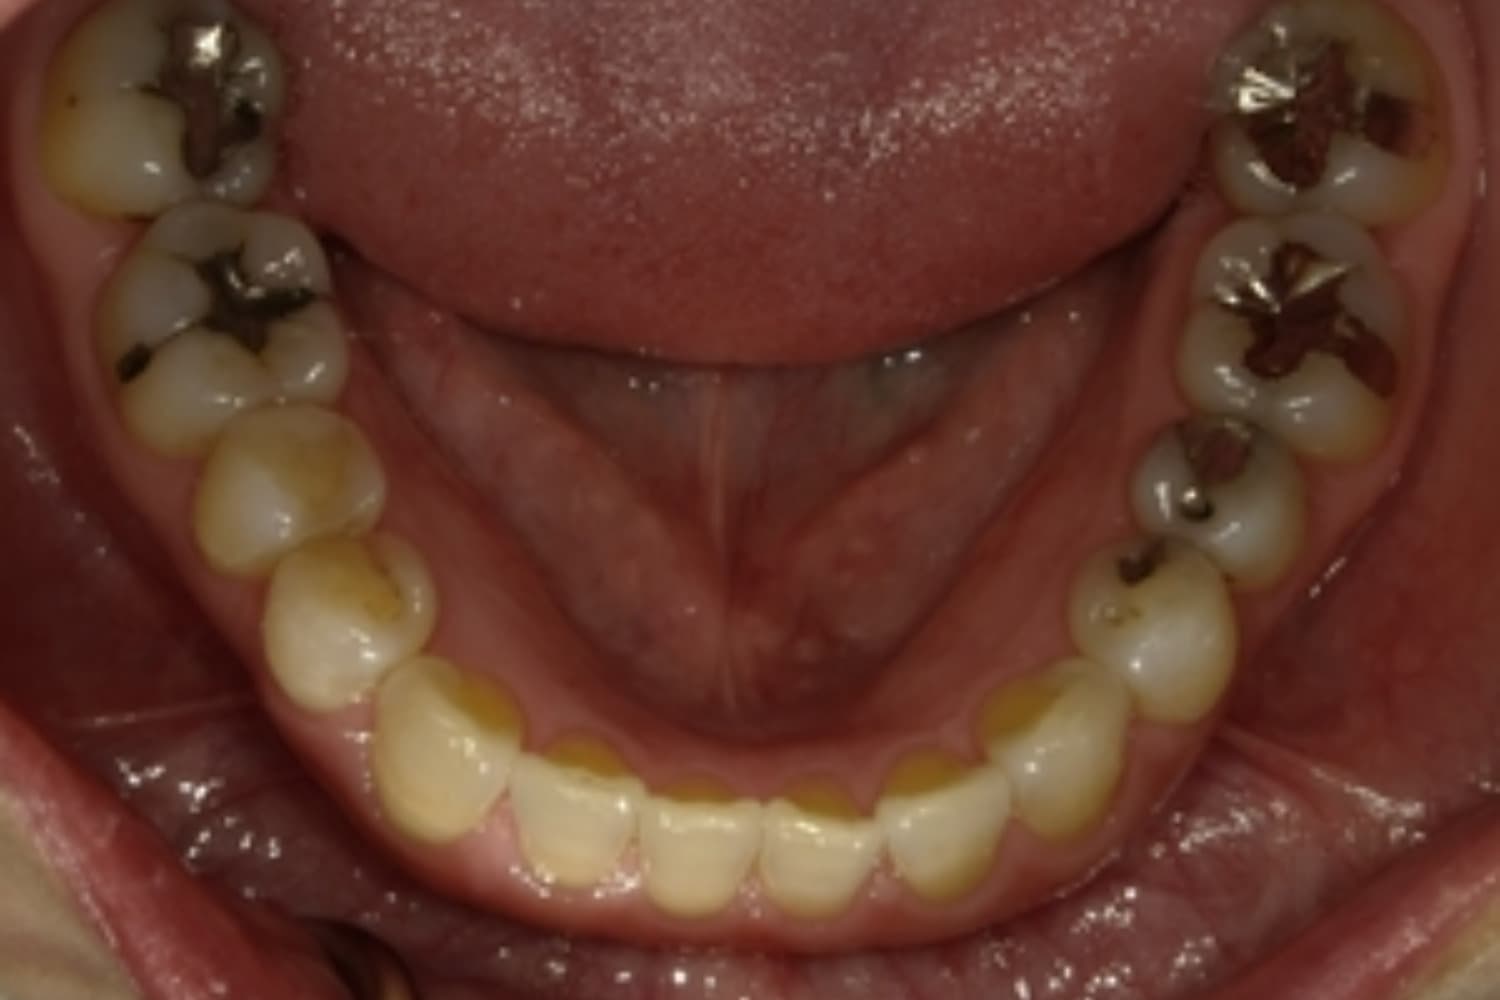

ガタガタとした歯並びや八重歯(1)

Before

After

ガタガタとした歯並びや八重歯をマウスピース矯正(インビザライン)にて治療

主訴

下の前歯のガタガタが気になる

治療期間

2年5カ月

費用

90万円